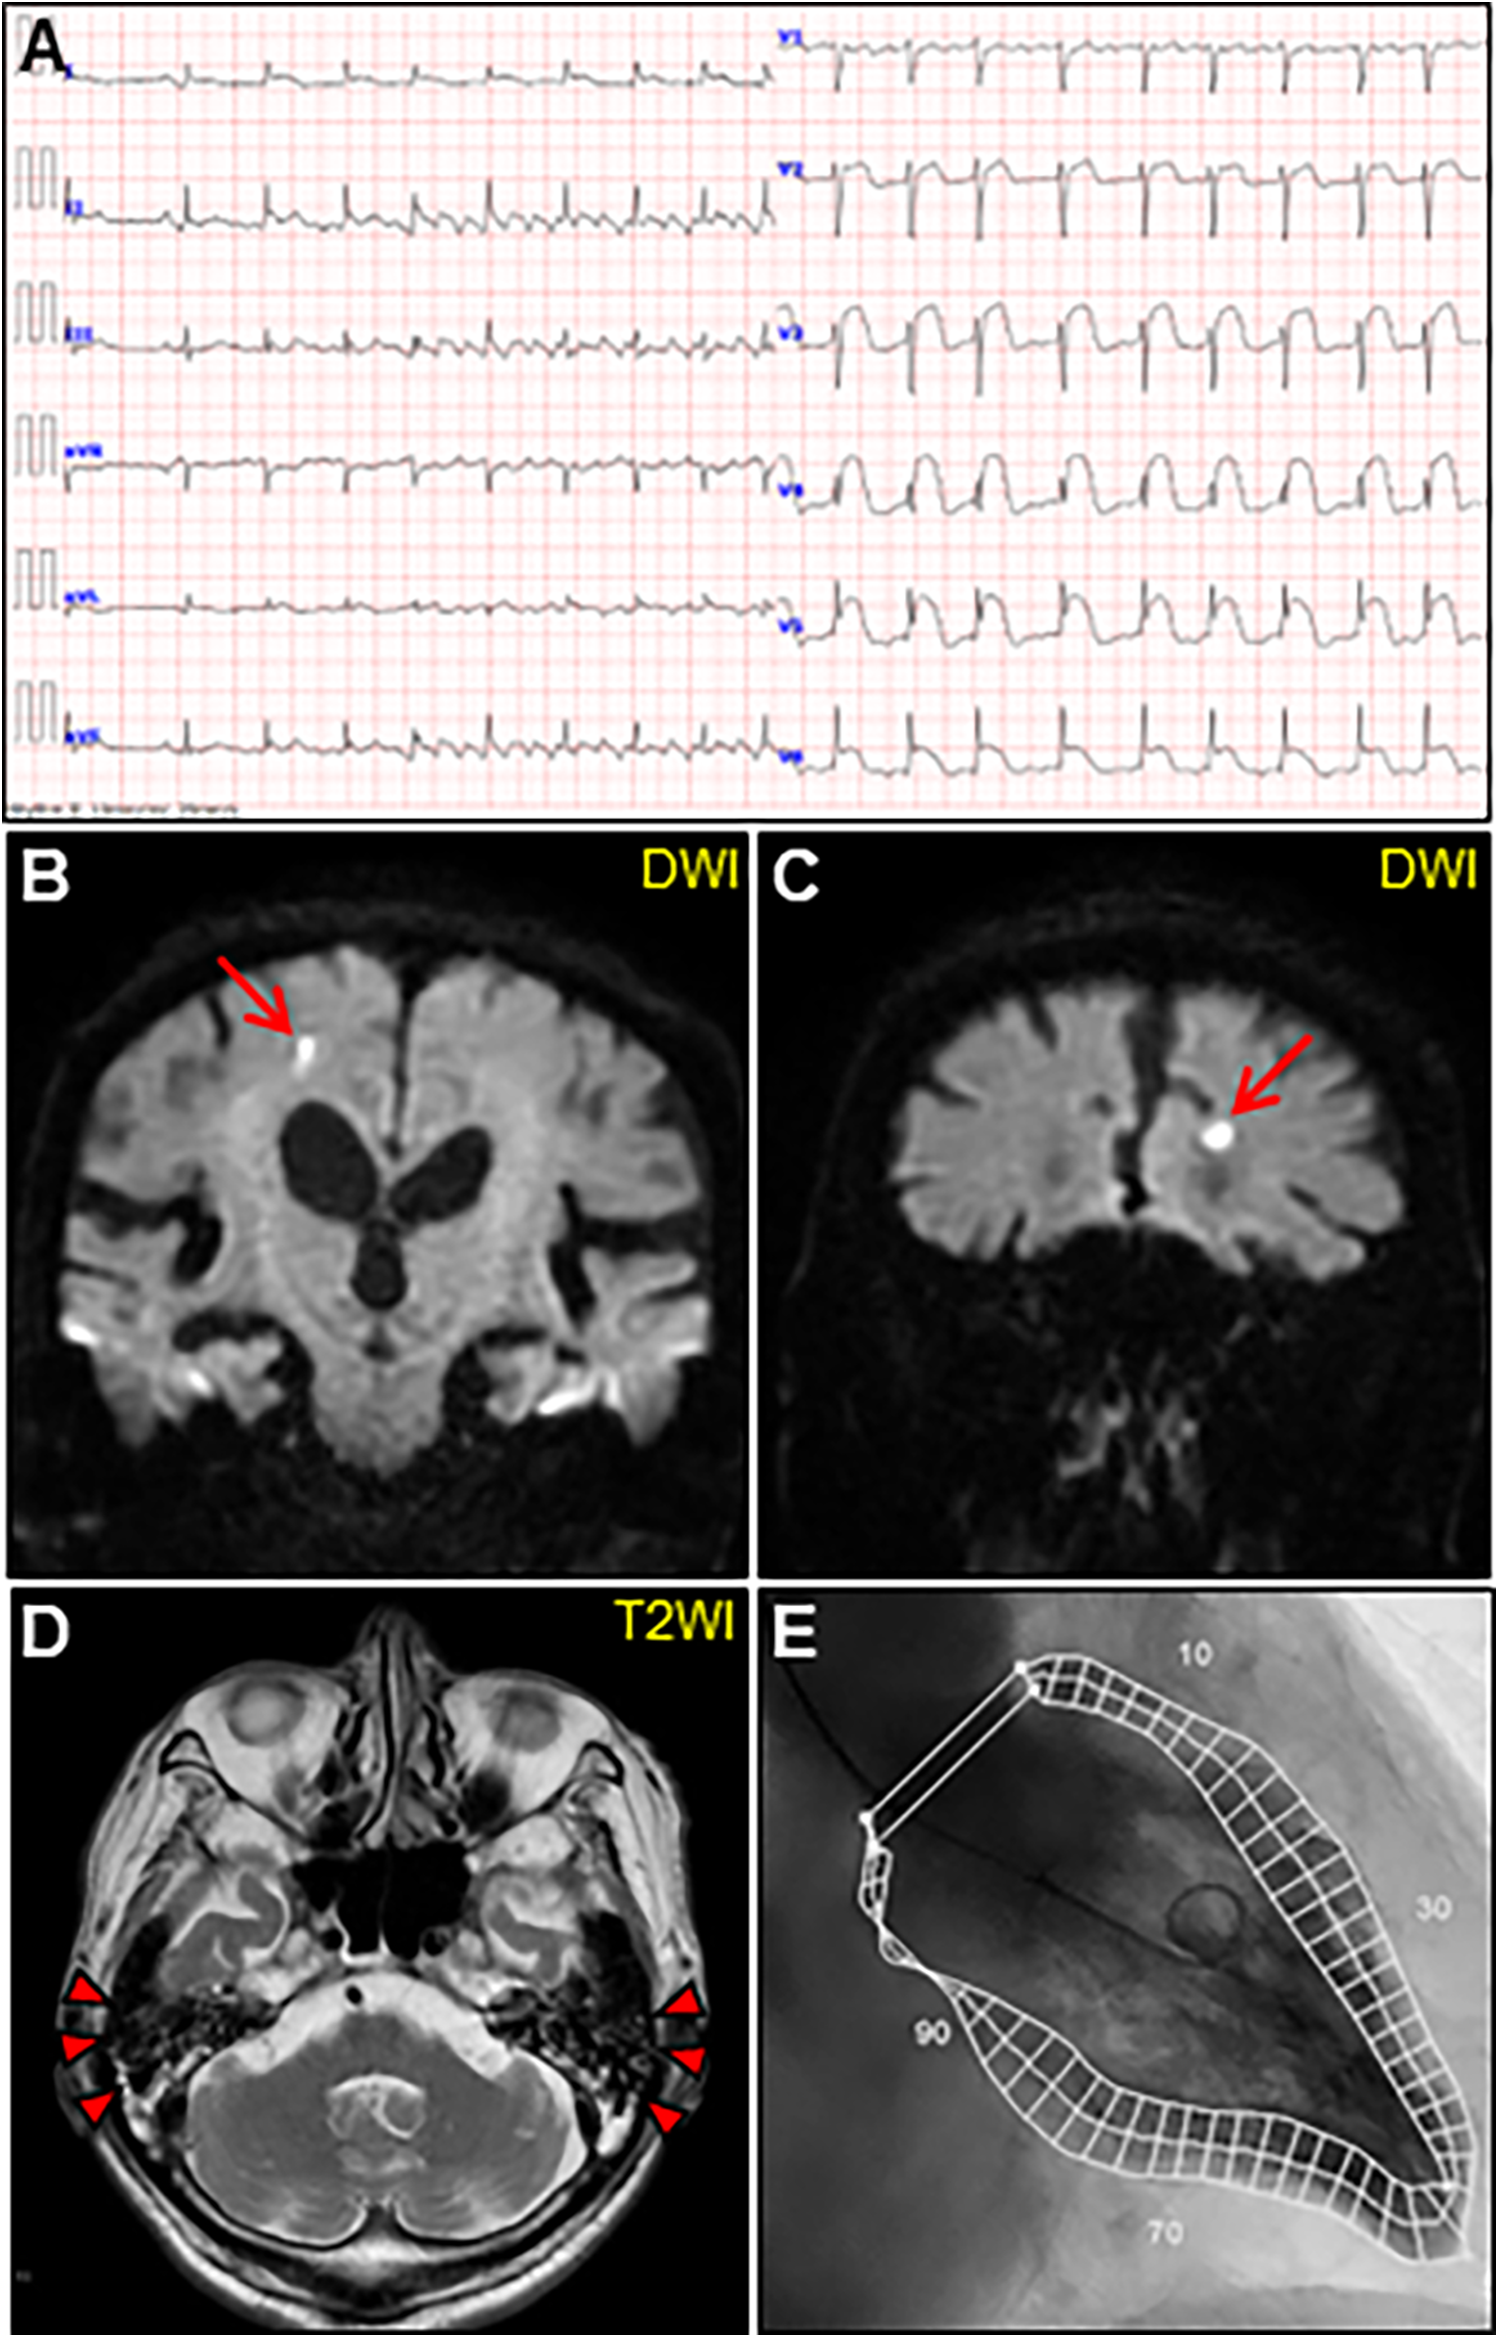

An 85-year-old man with high-grade fever, nausea, fatigue, and urinary disturbance was admitted to our hospital. The patient had a history of hypertension and benign prostatic hyperplasia, but no history of autoimmune gastrointestinal disorders. His vital signs were as follows: blood pressure, 160/102 mmHg; heart rate, 99 beats/min; and body temperature, 38.2°C. A physical examination revealed a distended abdomen. Abdominal computed tomography (CT) revealed an enlarged prostate gland with a distended bladder wall and bilateral hydronephrosis, suggesting a urinary obstruction. Empirical antimicrobial treatment with intravenous ceftriaxone was initiated for suspected urinary tract infection. On day 2, the patient became agitated, disoriented, and unable to follow instructions. Neurological examination revealed left hemiparesis and profound bilateral hearing loss. Electrocardiography showed atrial fibrillation with tachycardia and ST-segment elevation in the precordial leads (Figure 1A). Brain magnetic resonance imaging (MRI) revealed multiple cerebral emboli and bilateral acute otitis media (AOM) (Figures 1B–D). Laboratory tests revealed a white blood cell count of 6,200/μl without eosinophilia and an elevated C-reactive protein (CRP) level of 7.47 mg/dl (normal: <0.3 mg/dl). Additionally, elevated levels of serum cardiac troponin I (cTnI; 11,023 pg/ml, normal: <26.2 pg/ml) and N-terminal pro-brain natriuretic peptide (NT-proBNP; 885 pg/ml, normal: <125 pg/ml) were observed. Coronary angiography and left ventriculography were unremarkable (Figure 1E). Echocardiography revealed left ventricular (LV) hypertrophy, preserved LV contraction, and mild pericardial effusion. Enhanced CT indicated acute myocardial edema of the LV apex involving the anterolateral pupillary muscle (Figures 2A,B). Cardiac MRI established acute myocarditis (Figures 2C,D). The repeated urine and blood cultures remained sterile. The fever and inflammatory response without leukocytosis raised the suspicion of acute viral myocarditis with concomitant cardiogenic emboli. The patient underwent close telemetric monitoring with intravenous heparin infusion, followed by oral anticoagulant and anti-heart failure treatment. Furthermore, acetaminophen was administered for AOM. On day 6, the patient was transferred to the intensive care unit (ICU) due to cardiogenic shock, requiring intubation and catecholamine support. Follow-up electrocardiography revealed pathological Q waves with complete ST-segment resolution. Follow-up echocardiography revealed severe diffuse global hypokinesis with severe mitral regurgitation (Figures 2E,F; Supplementary Videos S1 and S2). Follow-up laboratory examinations revealed a greater increase in serum cTnI (18,946 pg/ml), NT-proBNP (35,000 pg/ml), and CRP (10.08 mg/dl) levels. Note the transient increase in the circulating absolute eosinophilic count to 542 cells/μl (Supplementary Figure S1). Repeated left ventriculography confirmed reduced global systolic function with an ejection fraction of 35%, followed by the insertion of an intra-aortic balloon pump (IABP). Subsequent endomyocardial biopsy (EMB) revealed numerous eosinophilic infiltrations admixed with CD3+/CD4 + helper T lymphocytes, macrophages, and adjacent cardiomyocyte injury (Figures 3A, B, D–F). Immunostaining for major basic proteins demonstrated extensive staining, predominantly eosinophils in the endocardium (Figure 3C), with macrophage polarization toward the M2 phenotype (Figures 3G,H). These findings confirmed a definitive diagnosis of acute eosinophilic myocarditis (AEM), which was treated with intravenous methylprednisolone (1 g/day for 3 days), followed by oral prednisolone (1 mg/kg/day) with gradual dose tapering. Thereafter, the patient remained hemodynamically stable. The IABP was weaned off on day 12, and the patient was transferred from the ICU to the general ward.

Figure 1. Initial examinations. (A) Initial electrocardiography. (B, C) Coronal views of brain diffusion-weighted magnetic resonance images (DWIs) showing multiple acute cerebral infarctions (arrows). (D) T2-weighted image (T2WI) showing fluid collection as a hyperintense area in bilateral mastoid cavities (arrowheads). (E) Left ventriculogram on day 2 after admission showing normal hyperkinetic contractions with an ejection fraction of 60%.